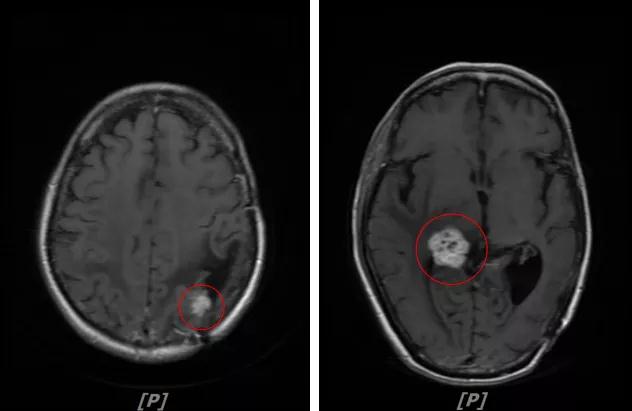

头颅增强MR:左侧顶颞叶见片状T1WI低信号、T2WI高信号影,病灶大部信号接近脑脊液,增强后术区边缘左侧顶叶见结节状强化影,大小约10x8x11mm,较2019-03- 15MR老片大致相仿;右侧脑室三角区见结节样T1WI等低信号、T2WI不均匀稍高信号影,增强后不均匀明显强化,大小约24x18x20mm,较2019-03-15MR老片明显增大;两侧半卵圆区、侧脑室旁见较对称片状T1WI低信号、T2WI高信号影,增强后未见明显强化,较前片相仿;余脑室、脑池、脑沟大小形态可,中线结构向左偏移。

左顶颞叶转移瘤治疗后改变

右侧脑室三角区旁强化结节,较2019-03-15MR老片明显增大 左侧顶叶强化结节,较2019-03-15MR老片大致相仿

两侧脑室旁云絮状异常信号,考虑放疗后改变